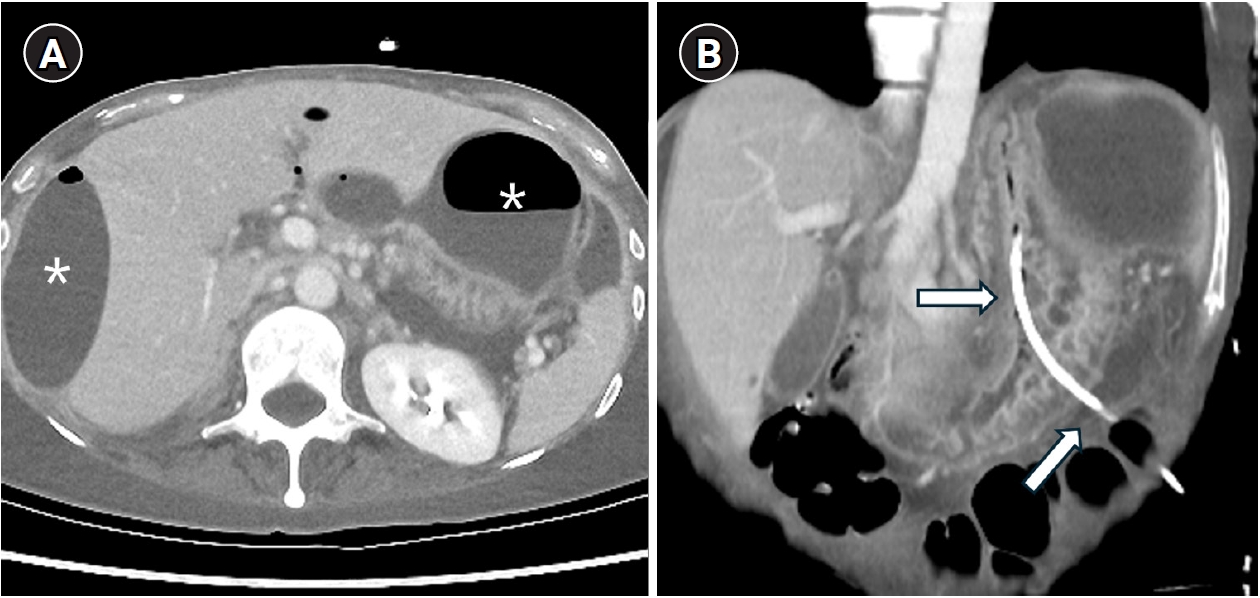

A 53-year-old woman with a history of total abdominal hysterectomy for endometrioid adenocarcinoma 2 years earlier and subsequent adjuvant chemoradiation therapy presented with adhesive ileus. She underwent adhesiolysis and small bowel resection; however, the surgery was complicated by anastomotic leakage, resulting in the formation of multifocal intraperitoneal abscesses. The perigastric abscess (

Fig. 1A) was accessed under ultrasonographic and fluoroscopic guidance. The following day, CT showed an 8.5-French PCD catheter located within the stomach (

Fig. 1B).

Fig. 1.A 53-year-old woman with a history of adhesiolysis for ileus presented with fever and abdominal pain. (A) Axial CT image shows multiloculated intraperitoneal fluid collections requiring drainage (asterisks). (B) Coronal CT image shows a percutaneous drainage catheter inadvertently placed within the stomach (arrows).